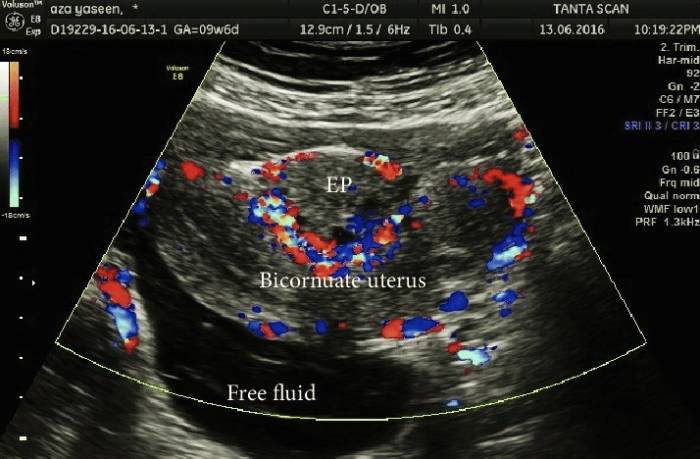

3. داپلر رنگی:

برای تهیه تصاویر در این نوع از سونوگرافی داپلر، از روش اولتراسوند استاندارد از عروق خونی استفاده می شود. در این نوع سونوگرافی داپلر کامپیوتر اصوات داپلر را به رنگی تبدیل می کند و پزشک با انجام آن می تواند از سرعت و جهت جریان خون درون رگ ها اطلاع یابد.